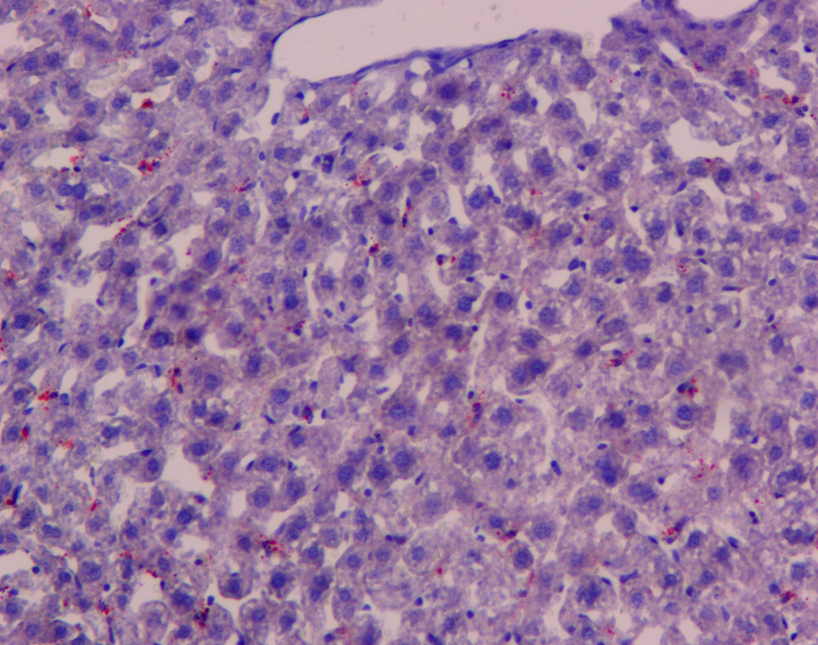

油紅O脂肪染色法是指在日常病理診斷和科研工作中為了顯示組織內(nèi)的脂肪常采用油紅O進(jìn)行染色的方法,油紅O為脂溶性染料,在脂肪內(nèi)能高度溶解,可特異性的使組織內(nèi)甘油三酯等中性脂肪著色。

【技術(shù)原理】

油紅O染色液主要用于顯示組織器官的脂肪變性和類脂質(zhì)的異常沉著,常發(fā)生于肝、腎、心等實(shí)質(zhì)臟器的脂肪變性,細(xì)胞內(nèi)出現(xiàn)多數(shù)中性脂肪滴;鑒別和診斷脂肪組織中所發(fā)生的腫瘤及其性質(zhì)。標(biāo)本不采用含有乙醇的固定液(如需要固定可采用 10%的福爾馬林)、也不采用石蠟切片,需用冰凍切片或碳蠟切片。脂肪的陽性染色結(jié)果呈橘黃至紅色,但具體顏色因脂質(zhì)濃度而定。

優(yōu)秀案例展示

中性脂肪 橙紅色或橘紅色

細(xì)胞核 藍(lán)色